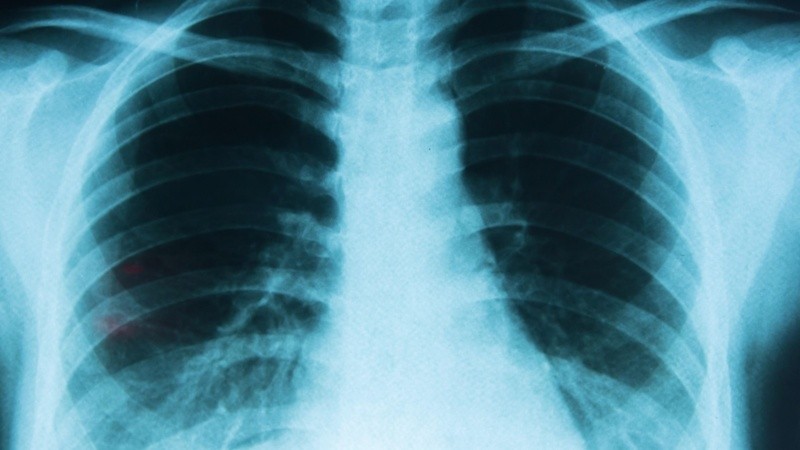

El cáncer de pulmón es el tipo de cáncer más prevalente y uno de los más agresivos; según las proyecciones para Argentina de la Agencia Internacional de Investigación sobre Cáncer (IARC) a partir de registros poblacionales, se estima que se detectan en el país 12.110 nuevos casos de cáncer de pulmón por año.

De acuerdo con el último reporte de Estadísticas Vitales de la Dirección de Estadísticas e Información de Salud (DEIS) del Ministerio de Salud de la Nación, en 2021 el cáncer de pulmón fue el de mayor mortalidad entre todos los tipos de cáncer: 8.740 fallecimientos, incluyendo pulmón, tráqueas y bronquios, lo que representa el 14% de todos los decesos por cáncer y el 2,1% del total de las muertes por causas identificadas.

Pese a que el cáncer de pulmón suele no dar síntomas hasta encontrarse en estadios avanzados, algunos signos permiten sospechar su presencia y ameritan una consulta médica con un especialista, tales como tos persistente o que empeora, tos con sangre, dolor de pecho, dificultades para respirar, sensación de cansancio permanente y pérdida de peso involuntaria.